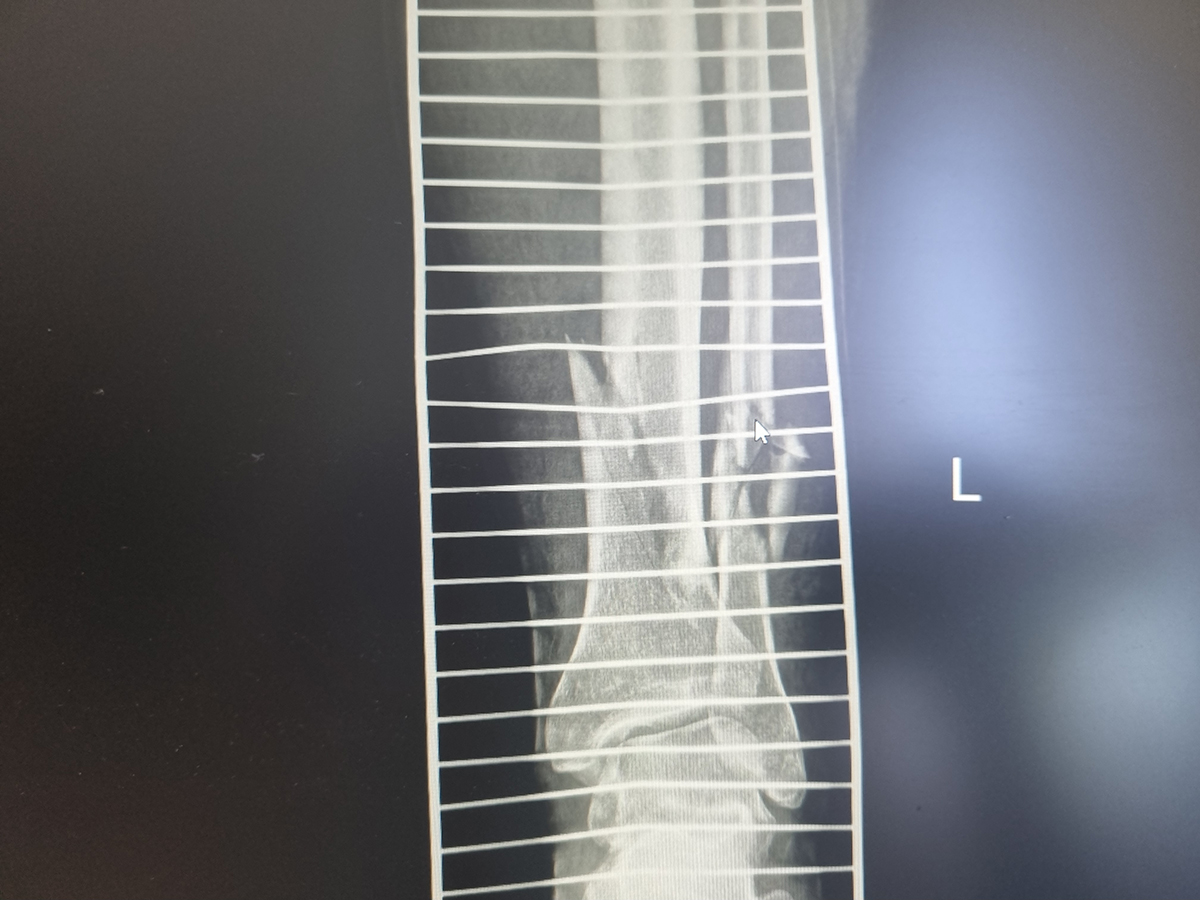

Zabiegi

Moja praca w RTG

Kończyna górna